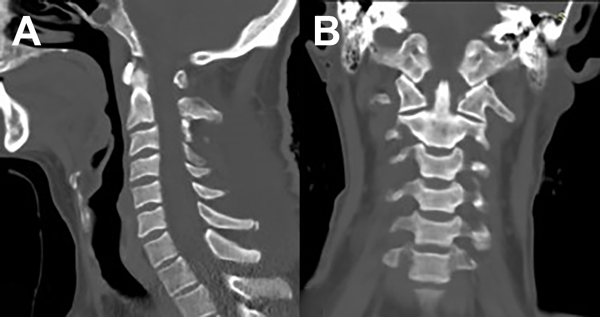

Se comprueba el grado de resección tumoral con RM de columna cervical confirmando la exéresis total macroscópica. Además, se realiza TC de columna cervical de control (Figuras 8 y 9).

Figura 8. RM de columna cervical. A) Secuencia T1. Corte sagital. B) Secuencia T2. Corte sagital. C) Secuencia T1 con contraste. Corte sagital.

Figura 9. TC de columna cervical. A) Corte sagital. B) Corte coronal.